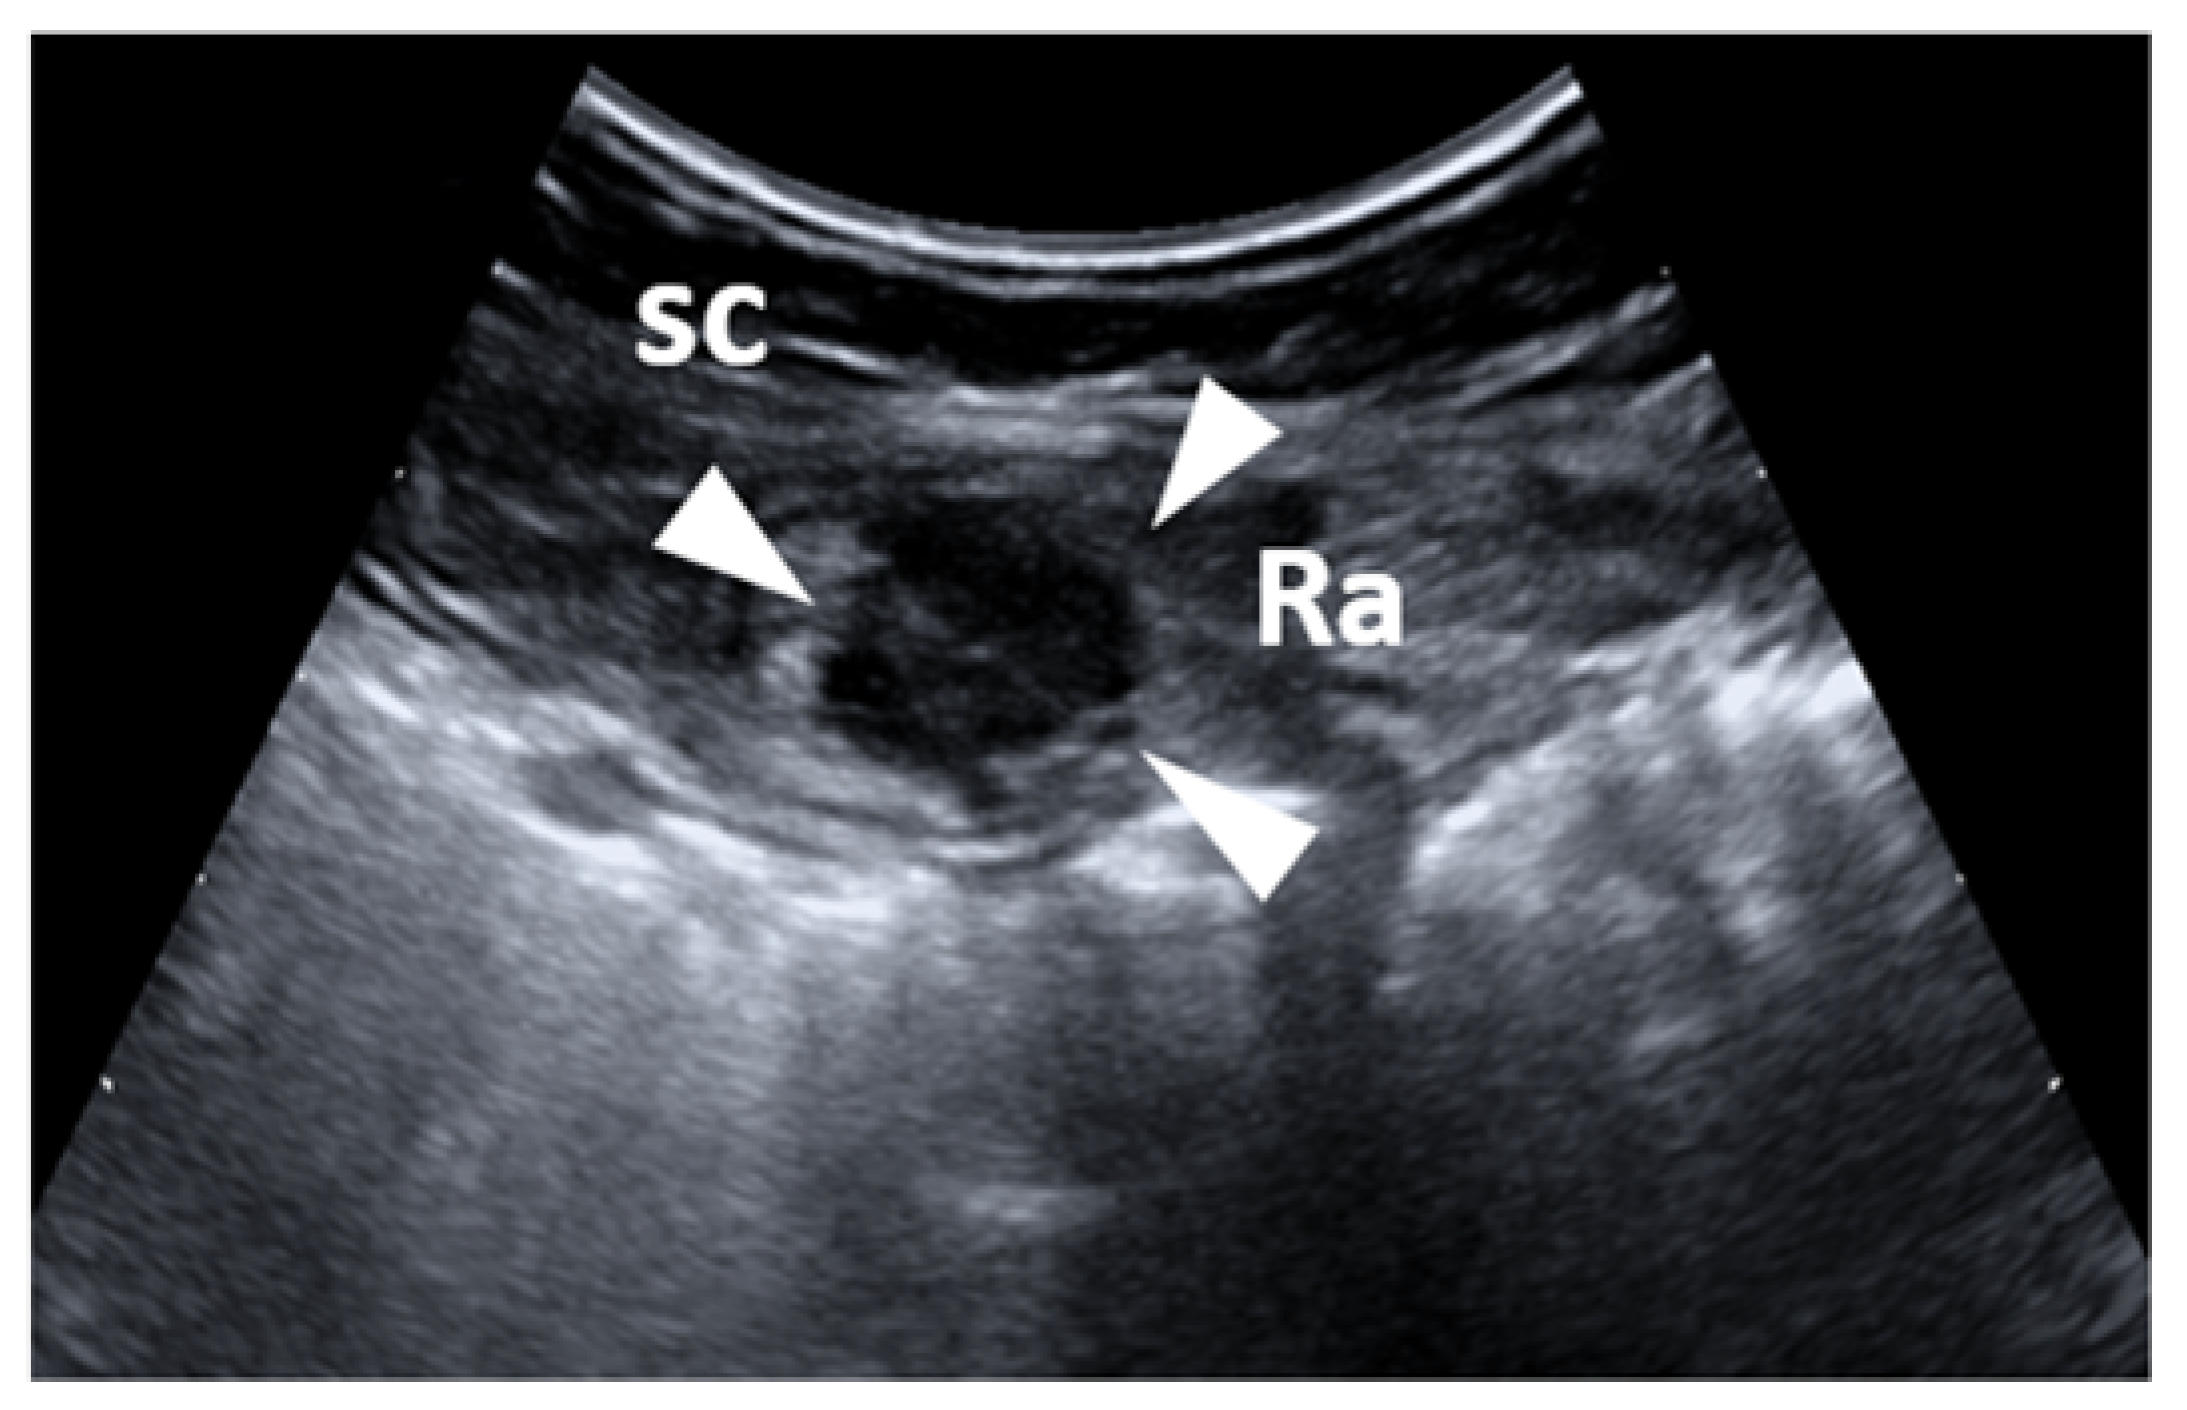

- Cocco, G.; Ricci, V.; Boccatonda, A.; Schiavone, C. Focused ultrasound for the diagnosis of non-palpable endometriotic lesions of the abdominal wall: A not-uncommon surgical complication. J. Ultrasound 2020, 23, 183–187. [Google Scholar] [CrossRef] [PubMed]

- Xie, M.; Zhang, X.; Zhan, J.; Ren, Y.; Wang, W. Potential role of strain elastography for detection of the extent of large-scar endometriosis. J. Ultrasound Med. 2013, 32, 1635–1642. [Google Scholar] [CrossRef]